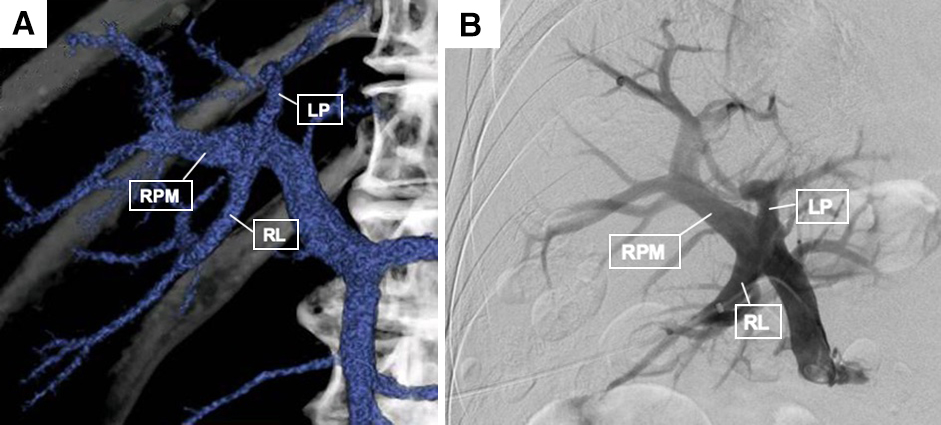

腹部ダイナミックCT所見:肝右葉,前後区域枝の分岐に近接して8.5 cm大の腫瘤性病変を認め,同病変は動脈相で濃染する部分を有し,門脈相で低吸収域を呈した.肝臓には他に腫瘤性病変を認めず,肺転移,腹膜播種,腹水を示唆する所見は認められなかった(Fig. 1).3D-CTによる門脈構築像では,門脈左枝・右前区域枝・右後区域枝はほぼ同時に分岐しており,Couinaud3)の分類で3分岐型と考えられた(Fig. 2A).

(A) 3D-CT image of the portal vein: Left portal vein (LP), right paramedian sector branch (RPM) and right lateral portal vein branch (RL) were almost branched at the same point. (B) Portography shows similar portal vein trifurcation.

以上より,肝細胞癌,T2N0M0 Stage II(原発性肝癌取扱い規約 第6版)と診断した.肝右葉切除を予定したが,術前のCT volumetryにて残肝予備能不足と判断し,切除に先立って門脈右枝に対して経皮経肝門脈塞栓術(percutaneous transhepatic portal embolization;以下,PTPEと略記)を行い,その3週間後に手術を施行した.PTPE時の門脈造影でも,上述のような同時分岐と考えられた(Fig. 2B).